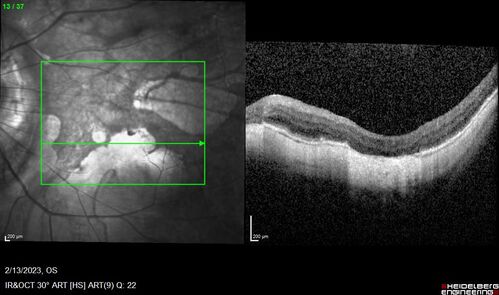

Myopic CNVM Left Eye

80 year old female. VA dropped to 20/125 but improved back up to 20/50 with Vabysmo